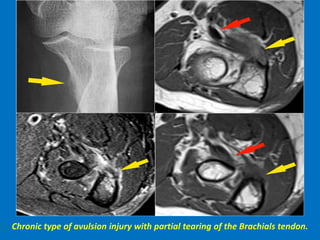

Chronic type of avulsion injury with partial tearing of the Brachials tendon.

Brachialis

muscle rupture.